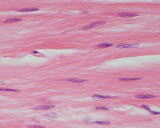

右図:組織が損傷すると線維芽細胞は形が楕円形になり、コラーゲンなどの細胞外マトリックスを多量に生産し、組織を修復しようとします。この組織は修復は途中でコラーゲンはまだらで、均一になっていません。均一できれいなコラーゲンが完成すると、線維芽細胞は左図のような線状形(非活動期)になります。